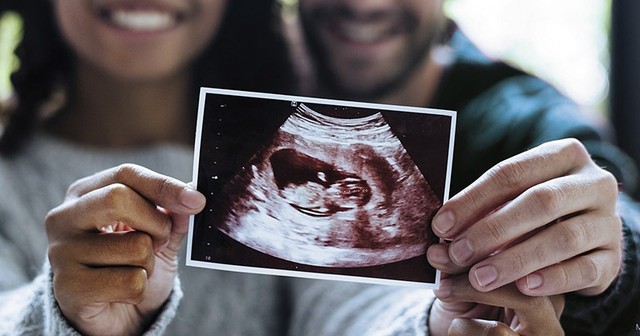

Khám thai định kỳ là việc làm vô cùng cần thiết giúp kiểm tra và theo dõi sức khoẻ của mẹ và sự phát triển của thai nhi trong thai kỳ. Một trong những chỉ số các mẹ nên quan tâm trong thai kỳ đó là độ mờ da gáy - đây là chỉ số thể hiện nguy cơ mắc hội chứng Down của thai nhi. Một câu hỏi đặt ra: Độ mờ da gáy 1.3 mm có bình thường không?